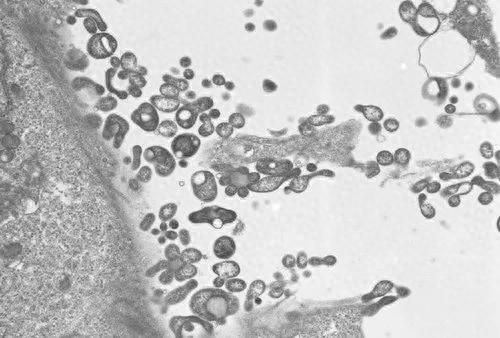

据俄罗斯塔斯社最新报道,世界卫生组织驻俄罗斯代表处负责人巴特尔·别尔德克雷切夫接受媒体采访时说,调查表明,俄罗斯境内没有出现“新病毒感染”,已知病例是由支原体感染引起了肺炎。

别尔德克雷切夫说,针对俄罗斯近来出现的咳血病例,世卫组织联系了俄罗斯相关机构。俄方按世卫组织要求提供了5例在莫斯科和莫斯科州登记的病例数据。经实验室研究确认,这5例病例所患疾病是支原体感染引起的肺炎,不是新病毒感染。